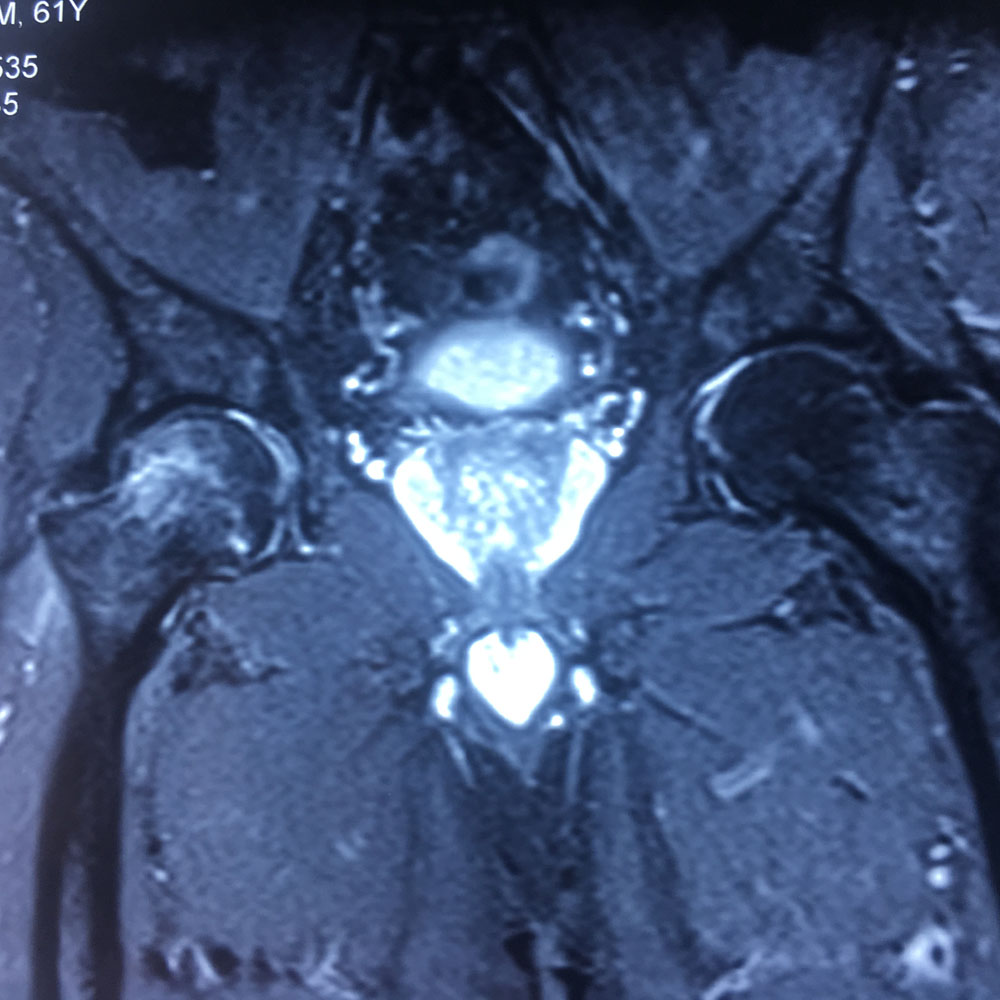

Εικόνα 3: Μαγνητική Τομογραφία του δεξιού ισχίου, στεφανιαίες (α-η) και εγκάρσιες (θ-ια) διατομές σε Τ1 και Τ2 ακολουθία, σε τρία επίπεδα. Σημειώνονται εκφυλιστικές αλλοιώσεις του δεξιού ισχίου, με στένωση του μεσαρθρίου διαστήματος. Ελέγχεται οίδημα με υπαρθρική κύστη στα άνω όρια της κεφαλής του αυχένα του δεξιού μηριαίου οστού. Ελέγχεται οίδημα των μαλακών μορίων παρά τα πρόσθια όρια του αυχένα του δεξιού μηριαίου οστού.